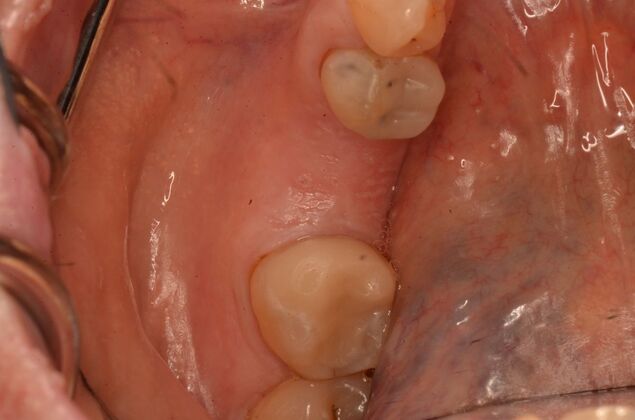

Patient lost lower first molars and required two lower implants with two lower screw retained crowns